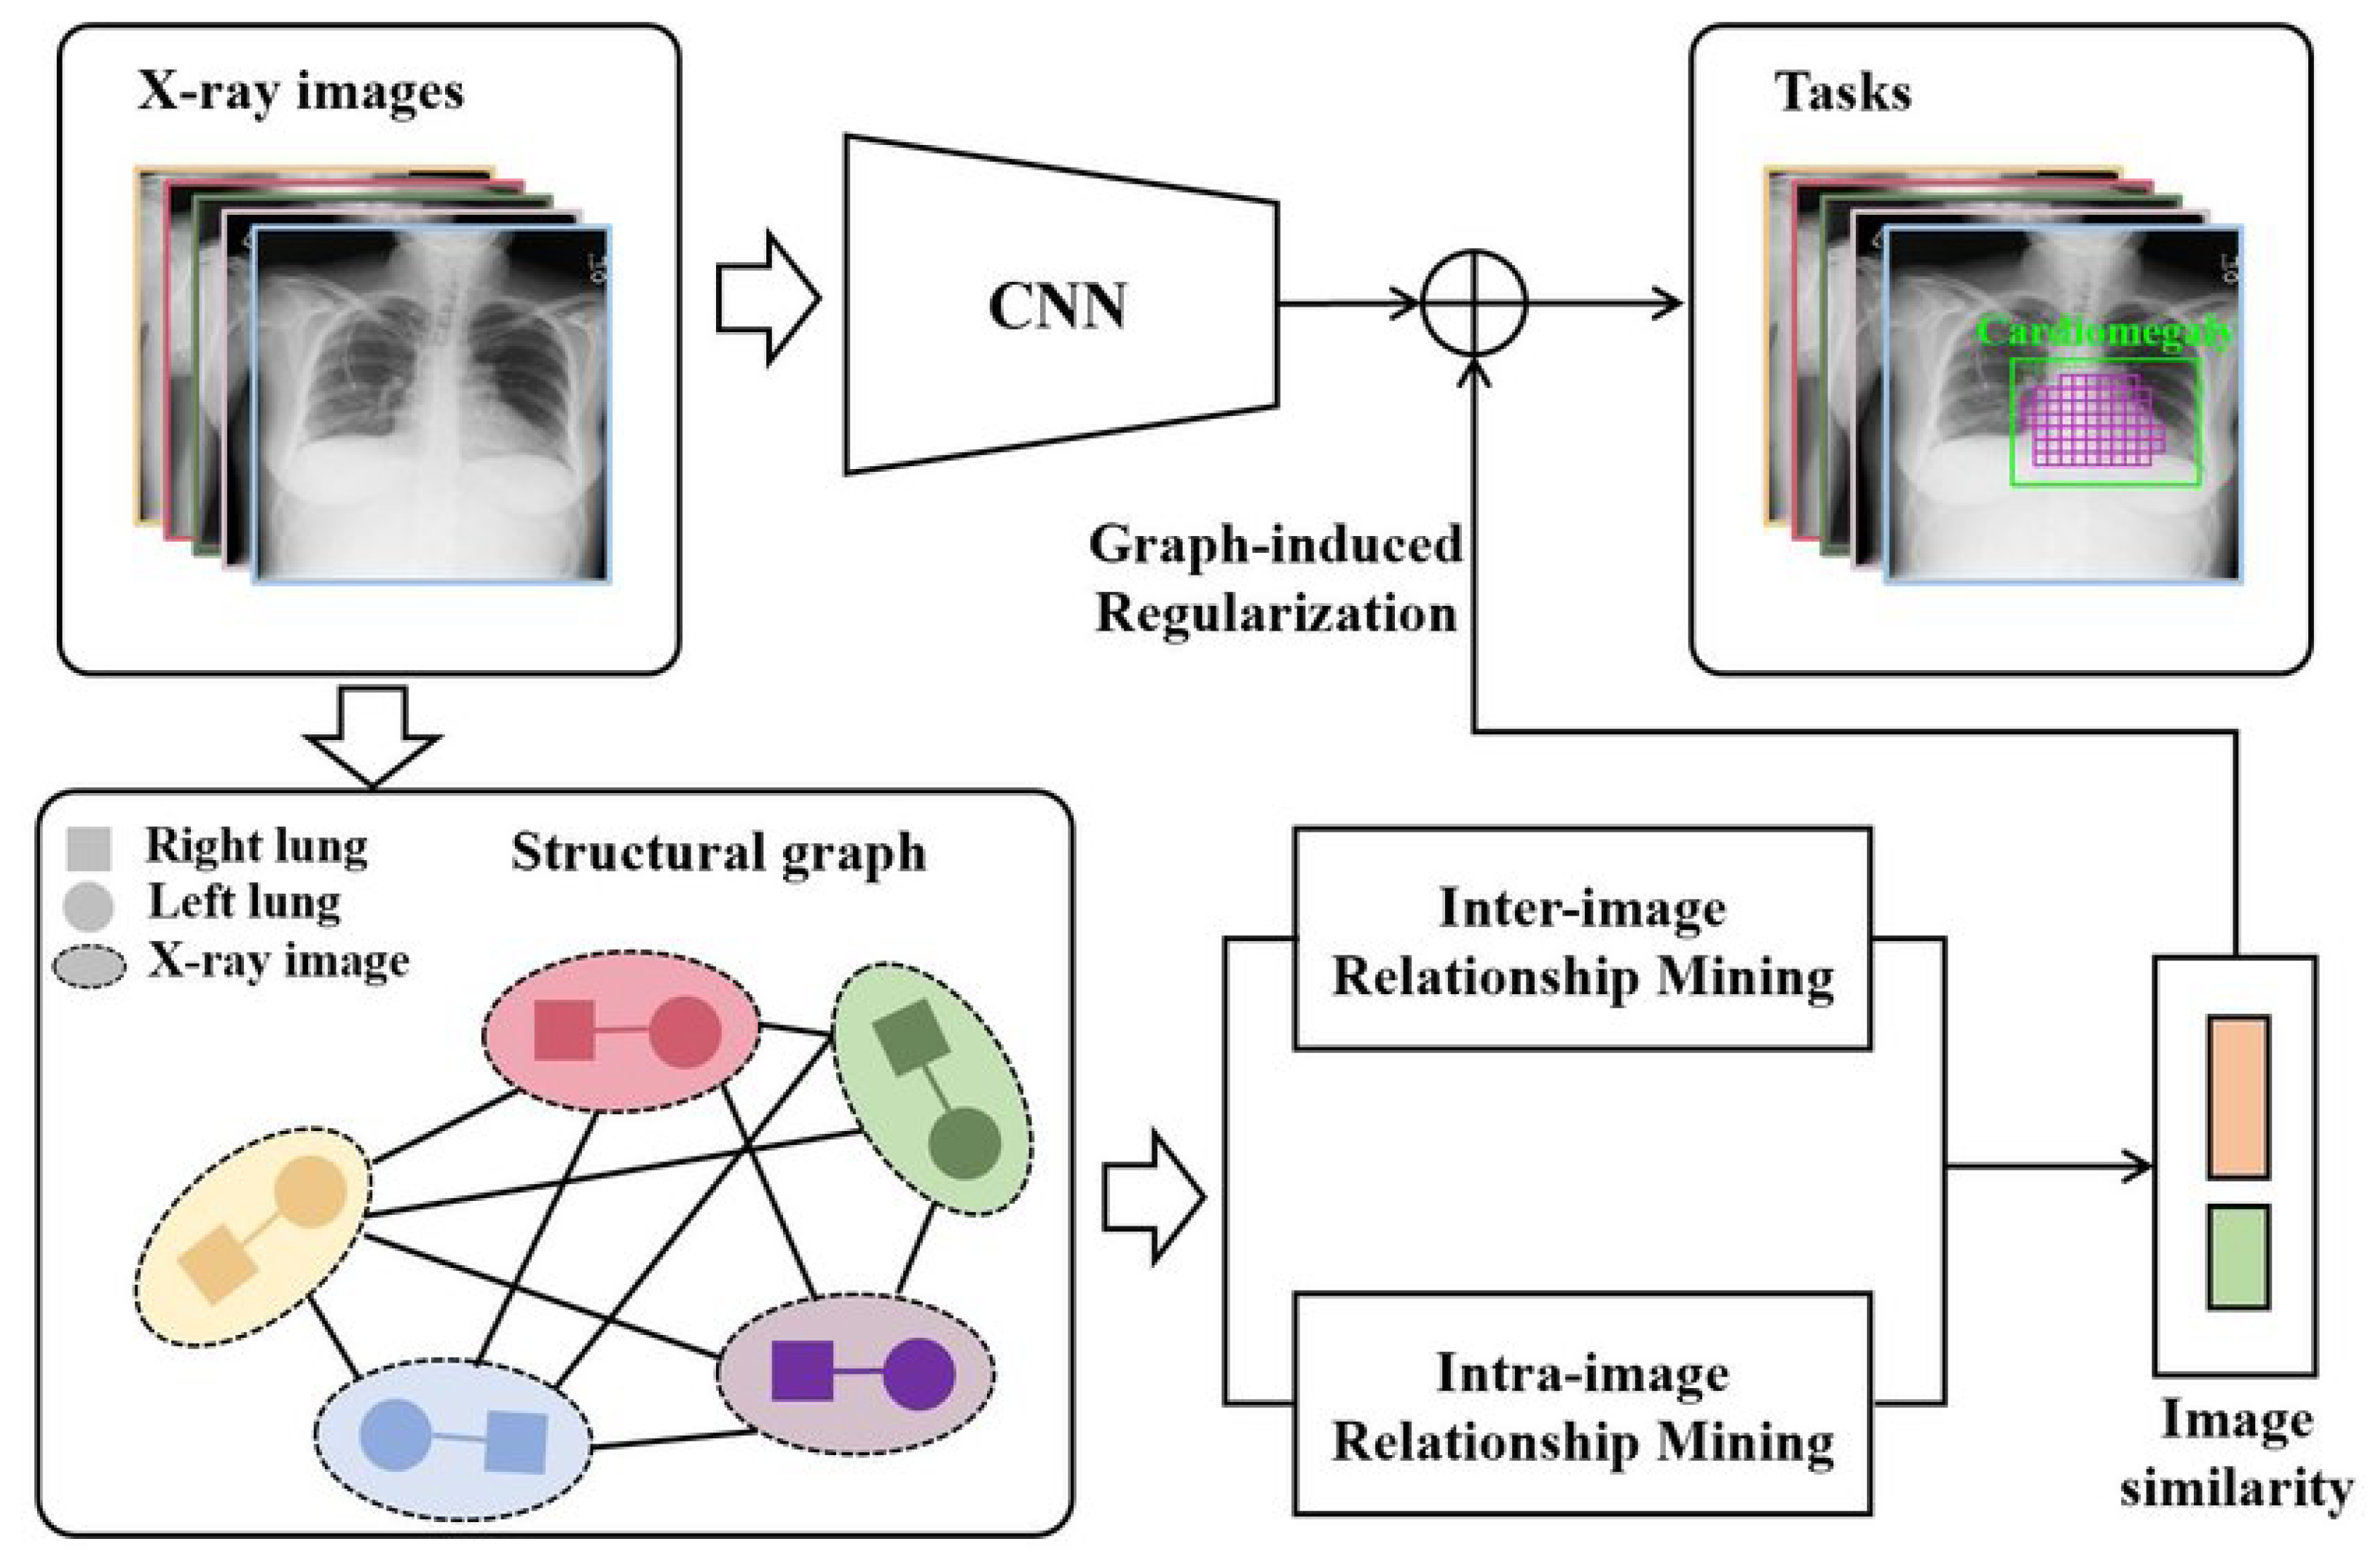

5.2. Graphical-Model-Based Weakly Supervised Segmentation

| Qi et al., 2021 [64] | Chest-Xray14 | Graph-Regularized Embedding Network (GREN) |